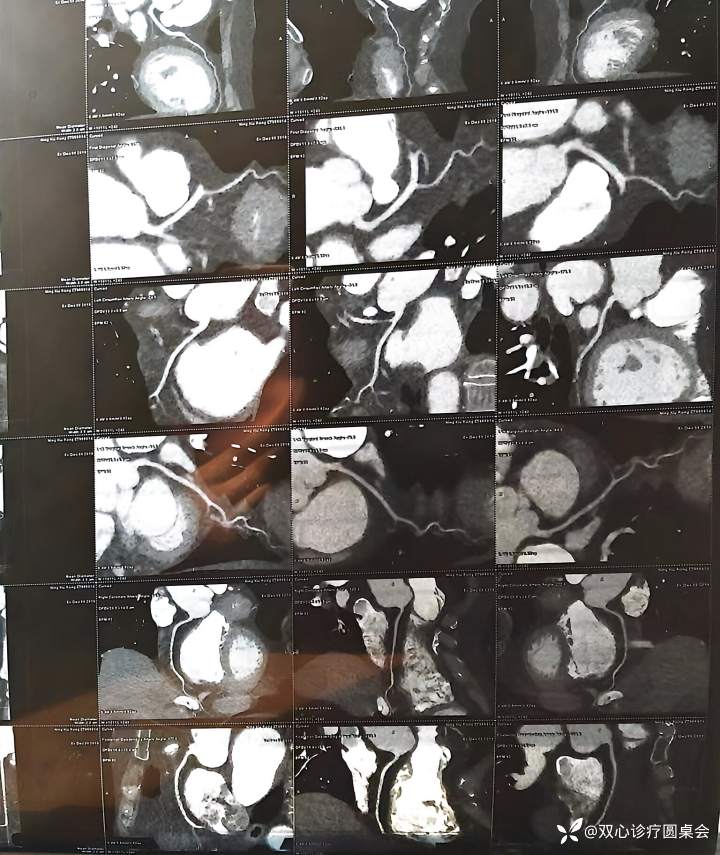

回顾既往检查

2022年 冠脉CTA

LM(—),LAD未见明显狭窄,LCX中段轻度狭窄,RCA未见明显狭窄。